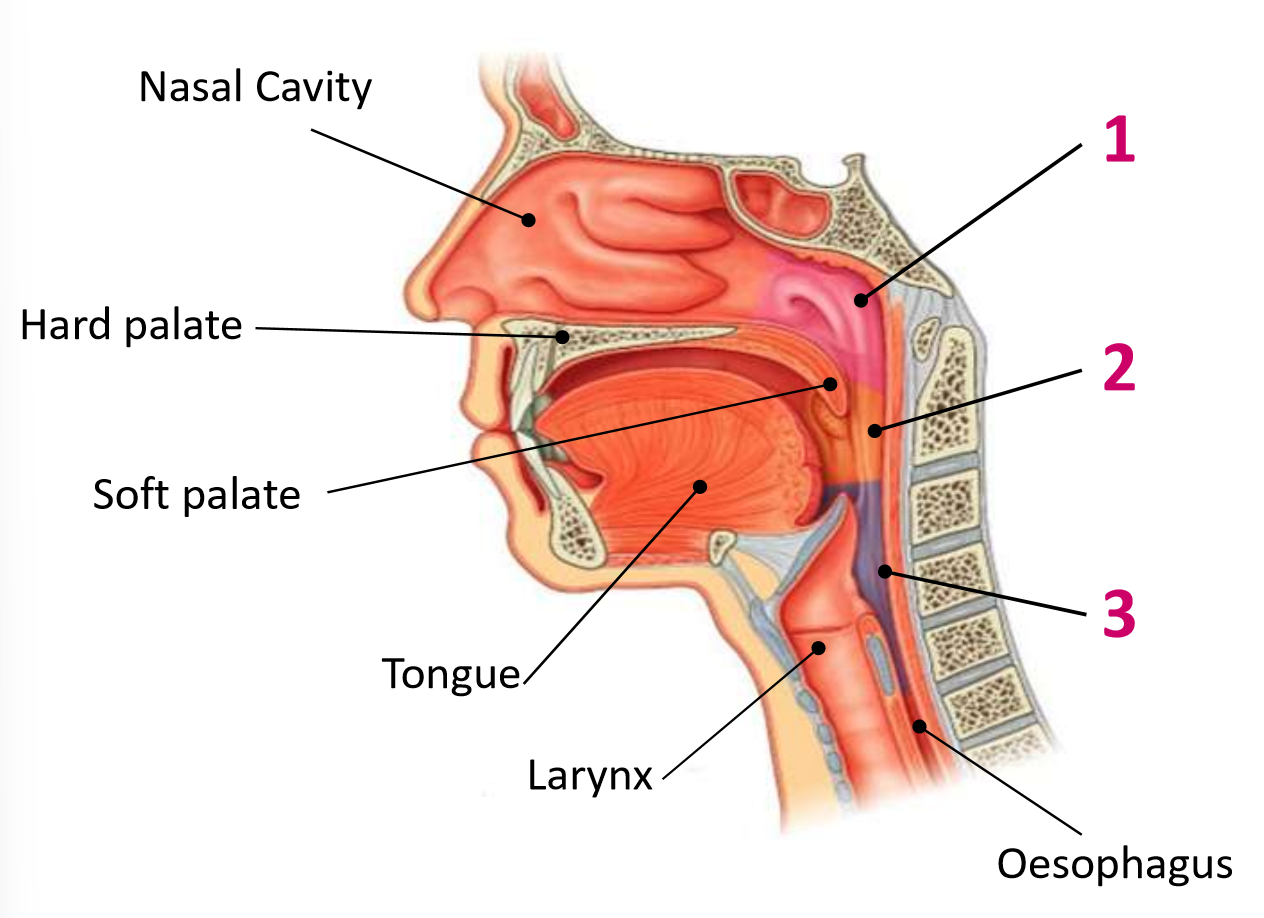

Which area of the head and neck do 1, 2, and 3 make?

pharynx

What region is 1?

nasopharynx

What region is 2?

oropharynx

What region is 3?

laryngopharynx

What is the anterior wall of 1?

posterior nasal choanae

What is the roof of 1?

body of sphenoid and basilar part of occipital

What is the posterior wall of 1?

anterior arch of atlas covered in pharyngobasilar fascia

What is the floor of 1?

soft palate

What is the anterior wall of 2?

oropharyngeal isthmus

What is the roof of 2?

soft palate

What is the floor of 2?

pharyngeal part of tongue and glossoepiglottic fold

What is the posterior wall of 2?

C2 and upper C3

What are the lateral walls of 2?

palatoglossal and palatopharyngeal arches